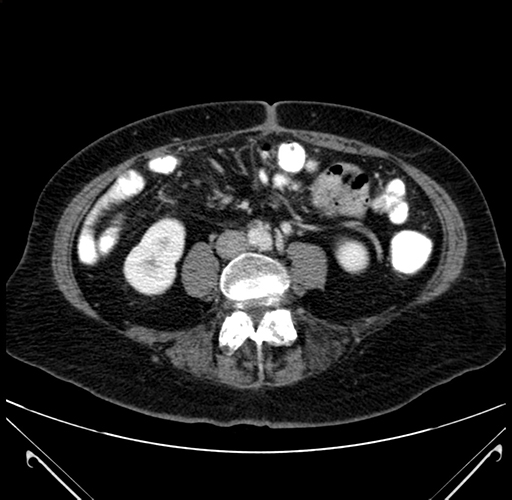

Axial Venous